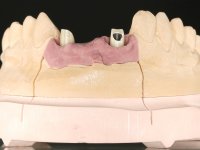

In the initial phase, it was proposed to the patient to perform the surgical implant exposure and after clinical evaluation, make prosthetic decisions. Once the healing screw was placed and the soft tissues were healed, an inadequate position of the implant was found. In view of the dramatic situation, the patient was proposed to remove the implant and put a new one after tissue regeneration. This proposal was rejected by the patient, who suggested temporary rehabilitation of the current implant. A new proposal was then made, to rehabilitate the implant, consisting of a screwed abutment, and on this, the placement of an acrylic crown with coronal and gingival components. After 6 years with the provisional treatment, the patient appeared in consultation with an abscess in tooth 1.1. After clinical and imaging analysis, it was decided to remove teeth 1.1 and 2.2, submerge the implant, place two implants at the site of 1.1 and 2.2 and perform adequate tissue regeneration. Temporization would be done with a provisional 3-element bridge, adhered with a net to the neighboring teeth. After osseointegration, definitive rehabilitation would be done with a 3-element bridge, including zirconia infrastructure and ceramic cover.

The surgical implant exposure and the healing screw placement proved to be a negative surprise regarding its position. Since the proposed removal of the implant was refused, we advanced to its provisional rehabilitation. An open tray impression technique was done, and a screwed abutment with a coronal and gingival component and an acrylic crown were made in the laboratory, using these two components. The provisional crown was placed in the mouth until a final decision was made. Six years passed before the patient returned to the clinic with an abscess on tooth 1.1. The choice to remove teeth 1.1 and 2.2 was made, to create a provisional 3-element bridge with a net to be adhered to the adjacent teeth. Surgery was planned and performed, placing the two implants at the site of 1.1 and 2.2, and the implant at the 2.1 site was cut with the objective of submerging it, while adequate tissue regeneration was performed (Surgical Work performed By Dr. Manuel Neves). During osseointegration, the patient used the fixed provisional bridge. A first impression was made for confection of a zirconia screwed provisional bridge, which worked the soft tissues for twelve weeks. The definitive impression was made with the individualisation of custom impression copings. Final rehabilitation was done with ceramized abutments, and also a bridge with zirconia infrastructure and ceramic cover. Due to the inclination of the implant placed at the site of tooth 1.1, the bridge required cemented fixation.